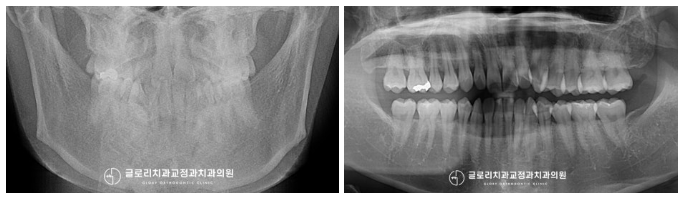

초진 사진을 보면 하악 전치부에 집중 된

치아 총생을 확인할 수 있었으며,

정중선 불일치로 인해 좌우 불균형이

나타나 있는 것을 확인할 수 있었습니다.

아래 앞니를 외에도 곳곳에

틀어지거나 삐뚤어진 치열이 많이 보이는데요.

골격적으로 별다른 문제는 발견되지 않았는데요.